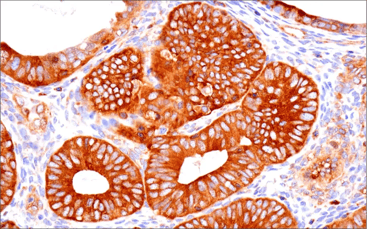

IHC analysis of paraffin-embedded human colon adenocarcinoma using Arginase-1 (D4E3M) Rabbit Monoclonal Antibody #93668 performed on the BOND RX autostainer by Leica Biosystems.